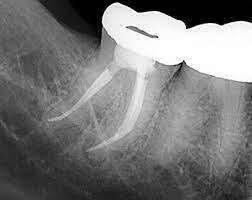

Rotary Endodontics

If you need root canal therapy, rotary endodontics may be your new best friend. Rotary endodontic technology ensures the root canal treatment is more efficient and comfortable.

This technology doesn’t require manually cleaning root canals. Instead, it uses a flexible nickel-titanium head to reach deeply into the canal to ensure every trace of infection is gently removed. Rotary endodontics also eliminates uncomfortable sensations often associated with manually-performed root canal treatment.